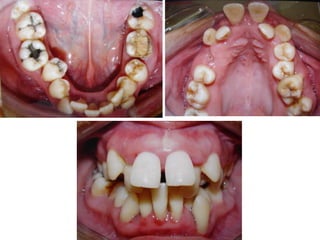

O documento descreve o tratamento de um paciente com incompetência labial, interferência lingual e deglutição atípica ao longo de vários anos, incluindo o uso de placas, remodelação transversal e guias de oclusão para corrigir problemas de alinhamento e contato dental. O paciente continuou com hábitos bucais indesejados apesar dos tratamentos realizados.